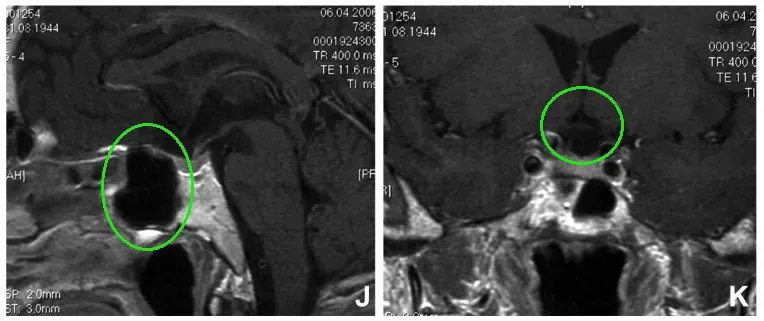

▼术后5年进行的t1加权增强矢状面(J)和冠状面(K)磁共振成像扫描显示无肿瘤残留或复发。